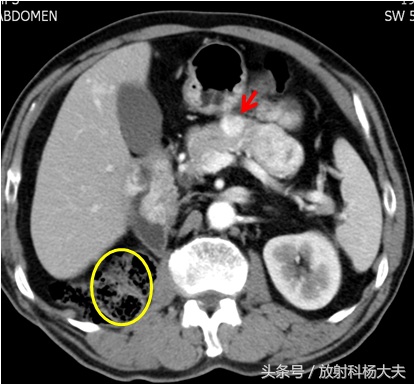

那这次胰腺有问题,会跟10年前的肾癌手术有关系吗?赶紧做增强CT吧。CT出来了,胰腺上长了一个不到一厘米的小瘤子,增强扫描明显强化,提示血供很丰富。

图中黄圆圈应该是右肾的位置,10年前因为肾癌全切掉了。红箭所示的白色结节就是胰腺的转移瘤,血供丰富

一般胰腺的肿瘤,比如常见的胰腺癌血供大多数不丰富,病人会出现体重下降,黄疸等症状。这个老人不符合。另外一种常见的血供丰富的肿瘤就是神经内分泌肿瘤,如乔布斯先生,就是恶性神经内分泌肿瘤肝转移的。多数会出现一些神经内分泌方面的症状,老人查了,各种激素都很好。那就剩一种可能,肾癌转移到胰腺了,老人的肾癌是一种叫透明细胞癌的常见类型,血供丰富,所以它的转移瘤也血供丰富。